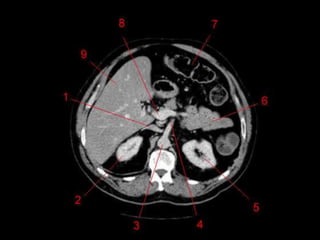

• TC: Tres fases

– Arterial (10 a 20 segundos)

– Fase venosa portal ( 30 segundos )

– Fase venosa hepática (60 segundos)

Técnicas de Imagem •US: Primeiro exame pedido ao: 1) dor no hipocondrio direito; 2) testes de função hepáticas anormais; 3) suspeita de malignidade. • TC: Tres fases – Arterial (10 a 20 segundos) – Fase venosa portal ( 30 segundos ) – Fase venosa hepática (60 segundos) • TC Portografia: Metastases.